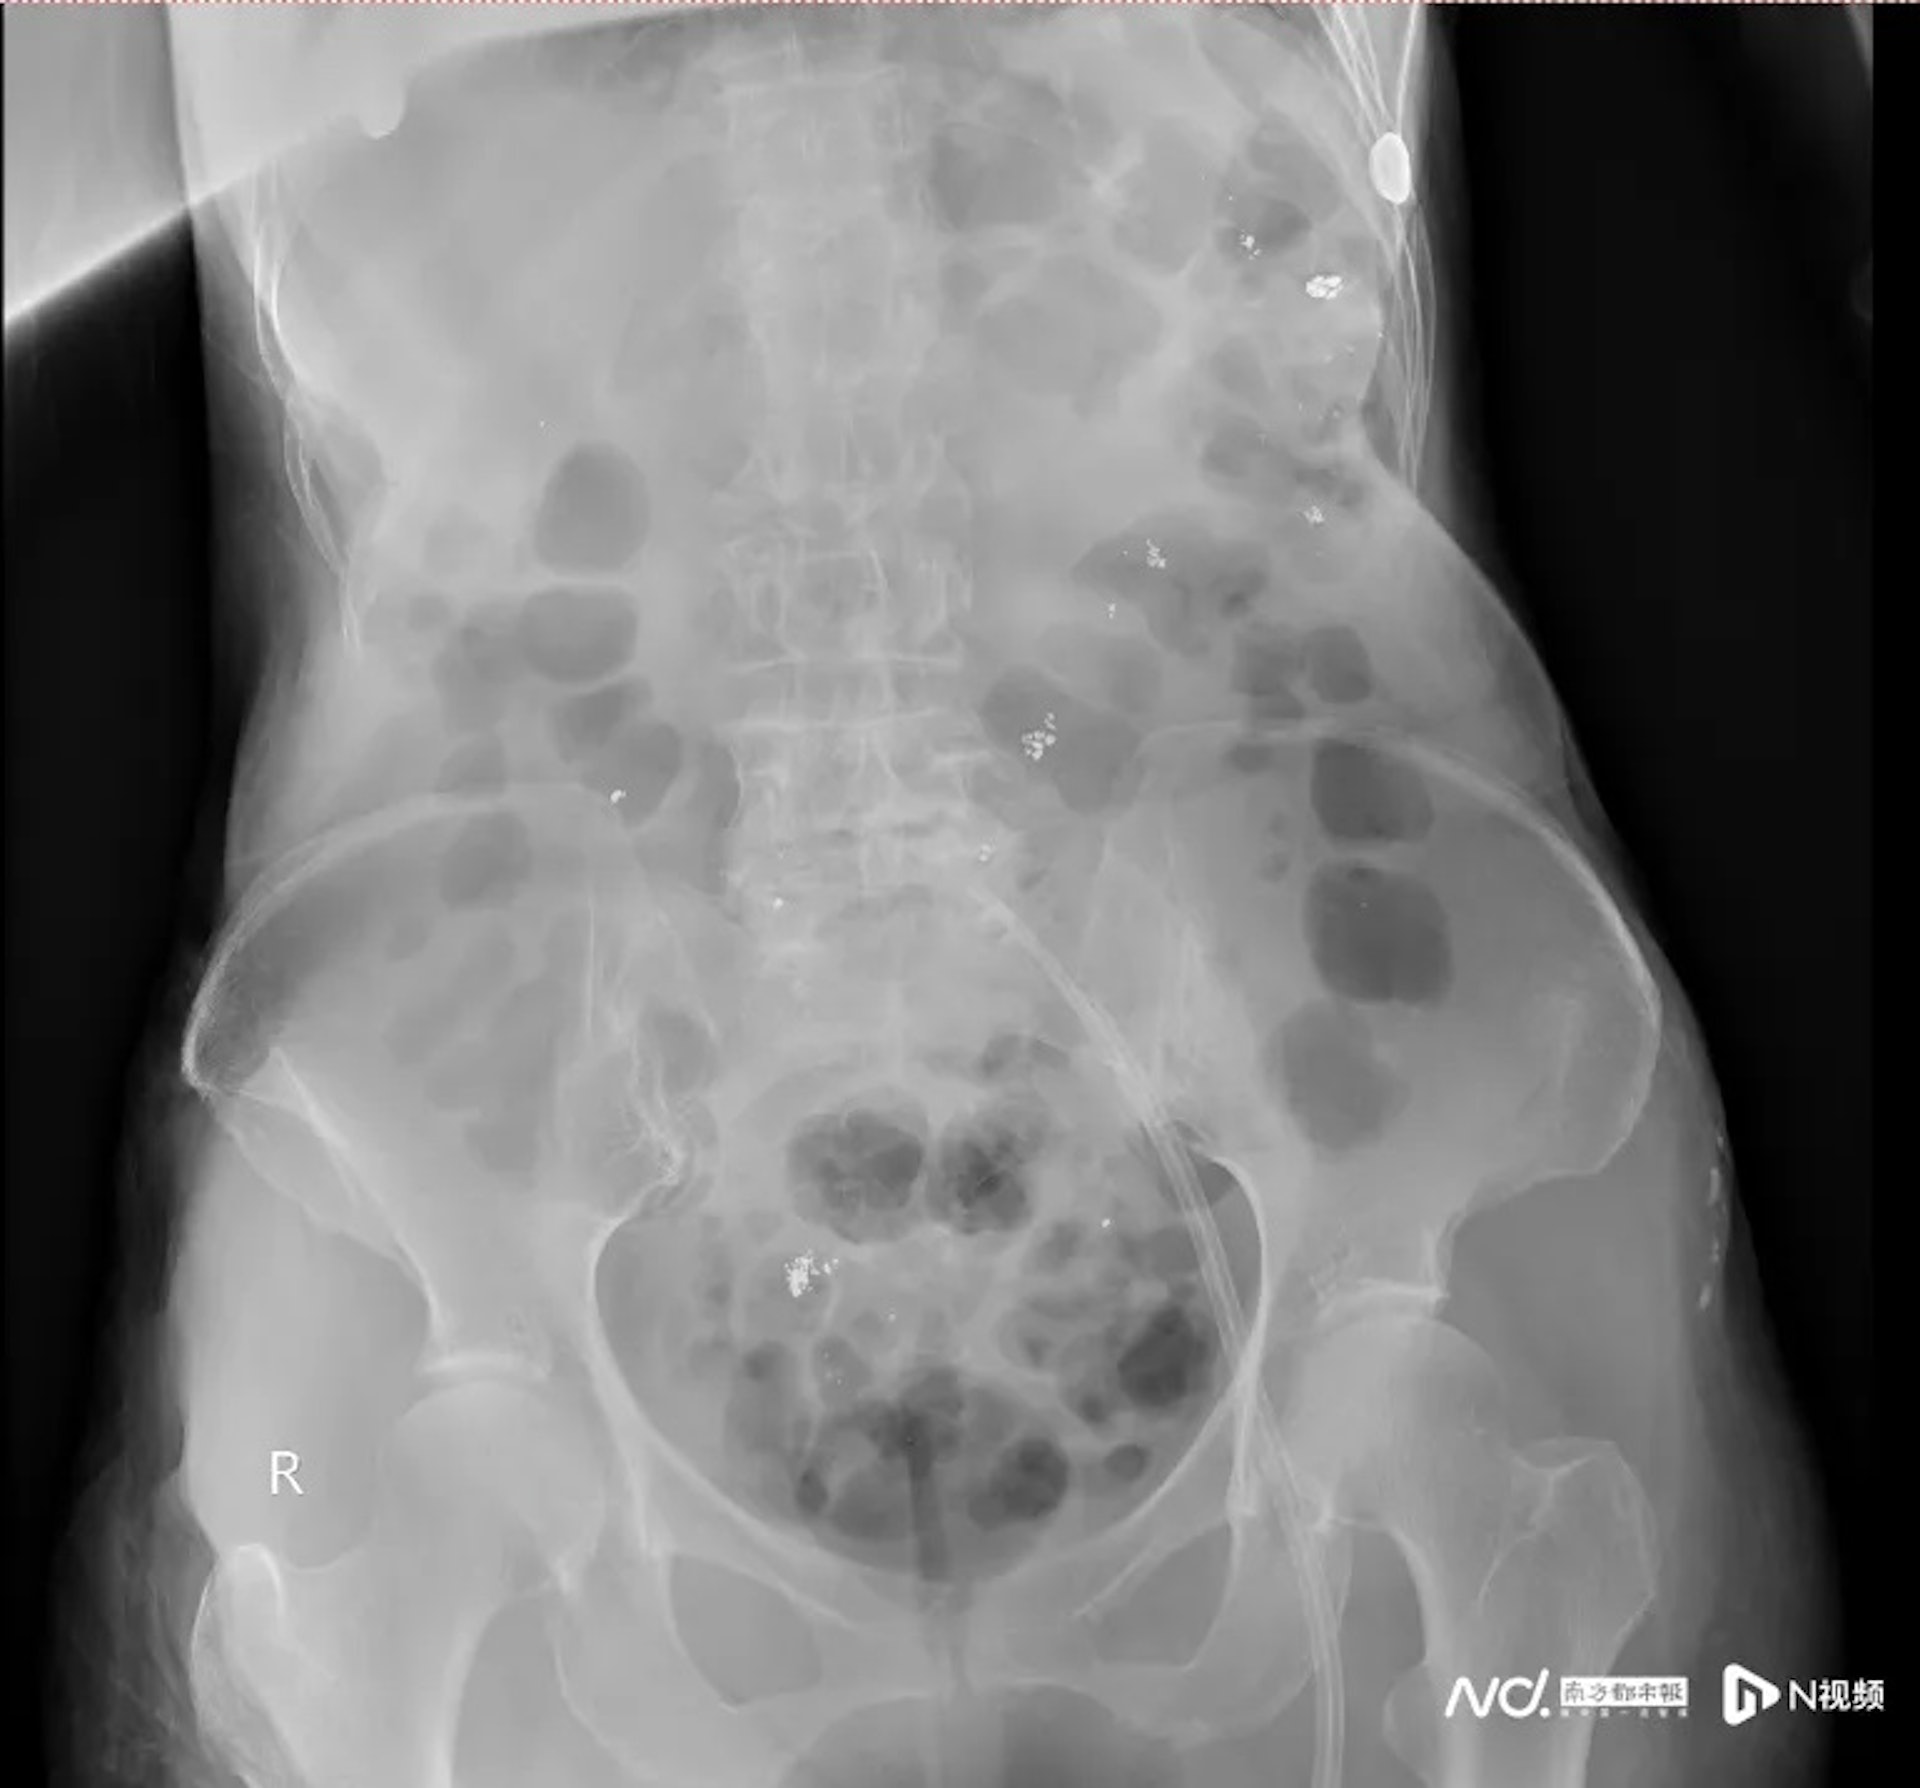

9 p$ Q" D4 E- f" t f& k6 n公仔箱論壇腹平片可以看到患者消化道內殘留大量汞。(南方都市報)